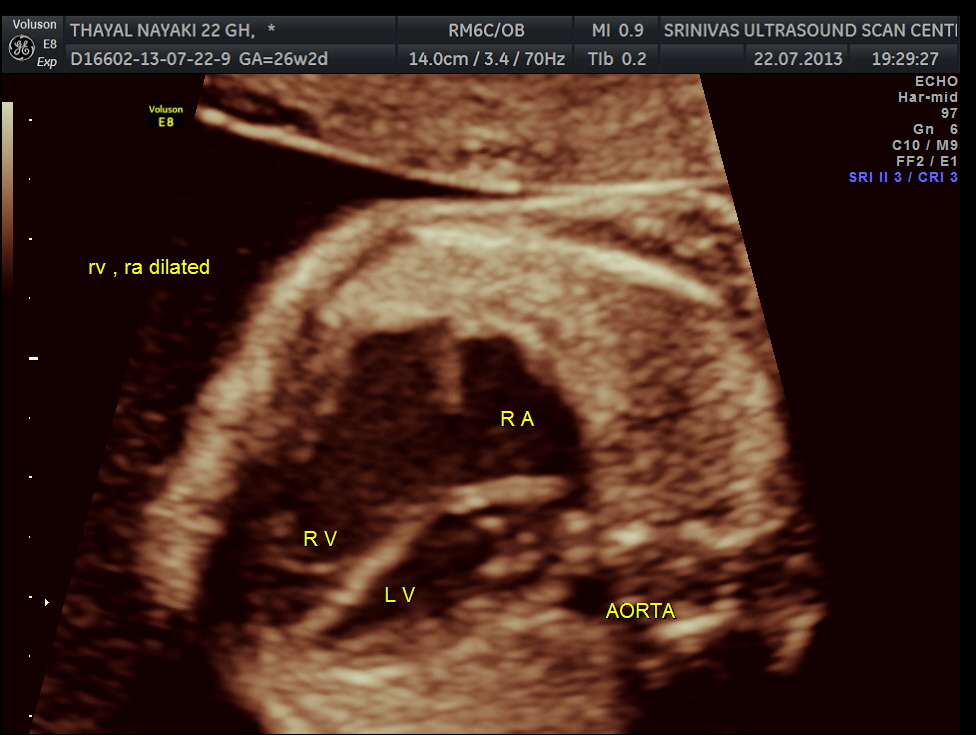

4 chamber view is given below .

3 vessel view shows a prominent single vessel , which is very suggestive of outflow tract anomalies like transposition of great arteries, double outlet right ventricle , truncus arteriosus and corrected transposition of great arteries.

Under normal circumstances the chamber in front of descending aorta is left atrium ; and the aorta arises from the left ventricle which has no trabeculations ; the pumonary artery which divides into the two branches arises from the anterior right ventricle and crosses over the aorta .

here we can see the pulmonary artery with its two branches arising from the lower (left) ventricle .and the aorta arising from the anterior (right ) ventricle.

Transposition of the great arteries (TGA) is the most common cyanotic congenital heart lesion that presents in neonates. The hallmark of transposition of the great arteries is ventriculoarterial discordance, in which the aorta arises from the morphologic right ventricle and the pulmonary artery arises from the morphologic left ventricle.